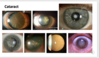

- Cataract = clouding of the lens -> age, diabetes, corticosteroids, congenital, trauma. Can be treated by surgery.

Cataract on image

Clouding of the lens

Age, diabetes, corticosteroids, congenital, trauma

Csn be treated by surgery